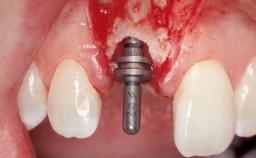

Immediate Flapless Placement of an Implant in a Maxillary Left Central Incisor Site

A 29-year-old female patient presented for treatment to replace the upper left central incisor tooth with an implant- supported restoration. The tooth had been intermittently symptomatic for the previous 12 months. The tooth had originally suffered trauma about 15 years previously. Several endodontic treatments had been performed, including an apicectomy procedure to retain the tooth. The patient was healthy and a non-smoker. She had reasonable expectations in regard to esthetic outcomes and the risk of marginal tissue recession following treatment. At medium smile, the gingival margins of the upper teeth were visible, with a display of 3 to 4 mm of the gingival margins. Gingival recession of tooth 21 and a discrepancy in the gingival levels between teeth 11 and 21 was observable during normal speech and smile.

| Attachment | One-Piece |

| Abutment Type | Customized |

| Placement Protocol | Immediate implant placement |

| Tooth Site | Maxillary incisor or canine |